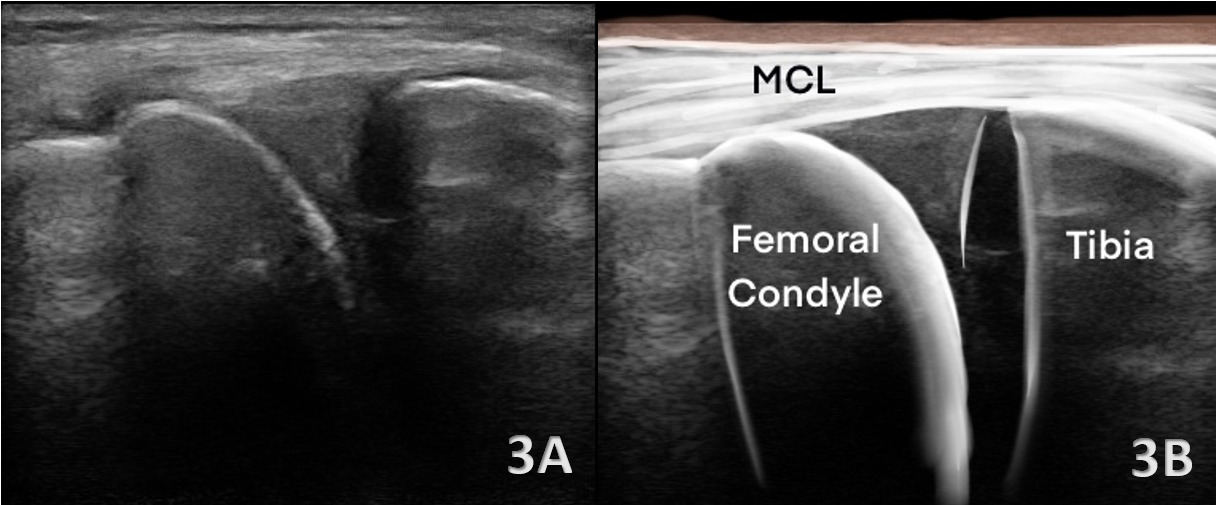

Medial Meniscus

Figures 3A and 3B LAX View of Medial Meniscus: The medial meniscus appears as a homogeneous, moderately hyperechoic, triangular structure positioned between the medial femoral condyle and the tibial plateau. The superior and inferior margins are smooth and well-defined. Sweeping the transducer from anterior to posterior allows visualization of the anterior horn, body, and posterior horn.